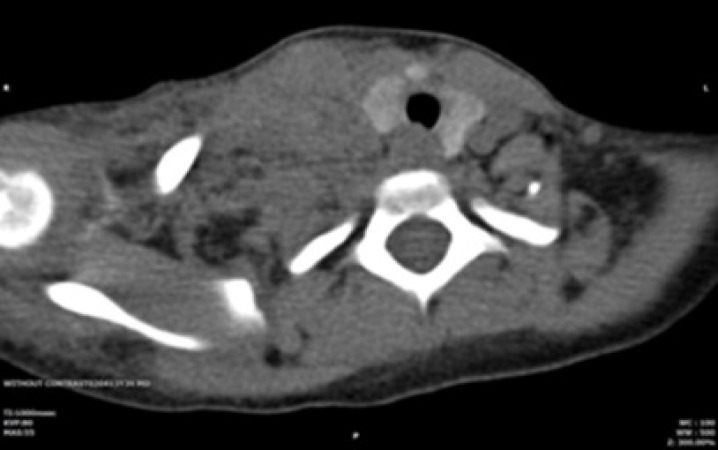

Horner syndrome, characterized by the triad of unilateral ptosis, miosis, and anhidrosis, typically arises following a stroke, surgical interventions in the neck and chest, or trauma. Horner syndrome is rare in children. This study presents the case of a 9-year-old girl with End-Stage Renal Disease (ESRD) caused by renal hypodysplasia. After permcath insertion, she developed a severe headache and anisocoria, followed by ptosis and a progressively expanding neck hematoma. Physical examination and MRI of the neck revealed that Horner syndrome, caused by hematoma formation following permcath placement, was the diagnosis. Supportive interventions were implemented, leading to significant improvement in Horner syndrome over a six-month period. Complications from permcath insertion can be a cause of Horner syndrome.